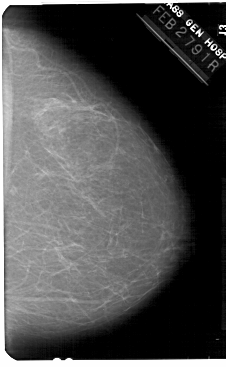

A_1375_1.RIGHT_MLO

RIGHT_MLO LINES 5491 PIXELS_PER_LINE 3706 BITS_PER_PIXEL 12 RESOLUTION 43.5 NON_OVERLAY